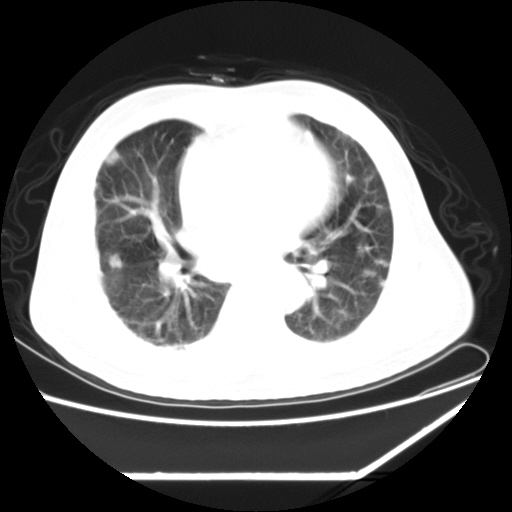

男,57,畏寒,发热

双肺多发结节样病灶,部分内见透光区,纵隔内见淋巴结肿大。结核临床如有畏寒,高热,白细胞增高首先考虑迁徙性肺脓肿(多是金黄色葡萄球菌感染)。

注意除外转移瘤。

1)考虑两肺感染性病变(金黄色葡萄球菌肺炎?);建议抗炎治疗后复查排除其他。2)双侧少量胸腔积液。

双肺典型的亚急性粟粒性肺结核

双侧胸膜结核